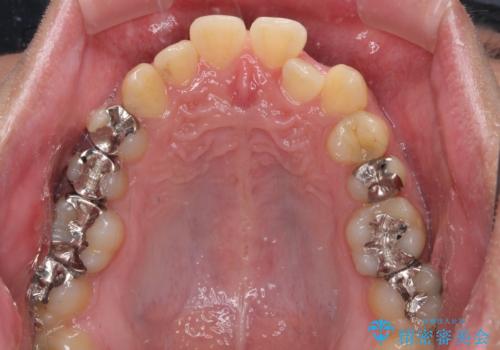

前歯のクロスバイト インビザラインによる矯正治療

- 上下のクロスバイトと前歯のデコボコを気にして来院された患者様です。

インビザラインを用い、IPR(歯と歯の間を削る)と歯列全体を拡大させることで、歯並びを整えていくこととしました。